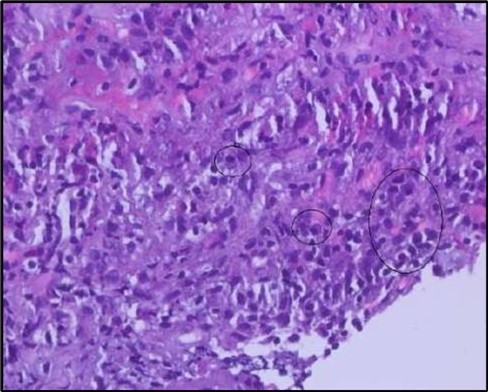

Figure 5b.OS, High-power H&E view showing dense inflammatory infiltration within the corneal stroma composed predominantly of lymphocytes and numerous plasma cells (circles highlight plasma cells).

OS, High-power H&E view showing dense inflammatory infiltration within the corneal stroma composed predominantly of lymphocytes and numerous plasma cells (circles highlight plasma cells).

Histopathological examination revealed a dense infiltration of CD138-positive plasma cells within the excised conjunctival tissue (Figure 5b, Figure 5c, Figure 5d). This finding supports an antibody-mediated immunopathogenesis in Mooren’s ulcer, consistent with Type II and Type III hypersensitivity mechanisms described in the literature 20, 21. The prominent presence of CD138- positive plasma cells provide a clear pathological rationale for conjunctival resection, as excision of the immunologically active perilimbal conjunctiva effectively removes the local 'factory' of autoantibodies that drive corneal stromal destruction, thereby halting ongoing tissue damage 21.